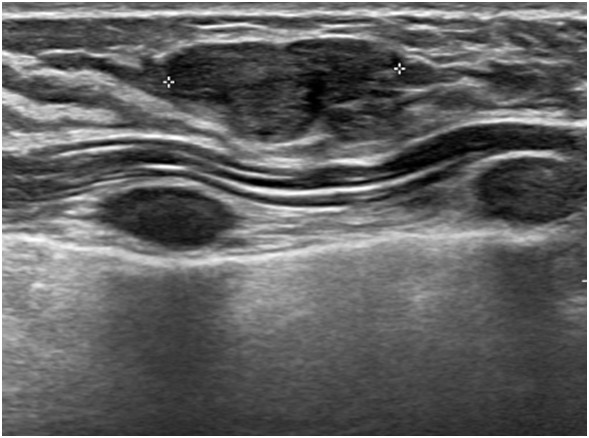

常珮雲說,乳房超音波可發現許多良性的病兆,例如纖維腺瘤、纖維囊腫、脂肪瘤、淋巴結腫大、鈣化、隆乳的植入物是否滲漏或術後導致的乳房結構異常等。且因乳房超音波沒有輻射,因此某些族群非常適合做這項檢查,簡述如下:

2.超音波適用於年輕女性,因為年輕女性乳腺較緻密發達,若用於乳房攝影時影像上緻密的乳腺及病灶顏色會相近,較難以區分判讀;但若於超音波有發現病灶且須進一步追蹤時,還是需要加照乳房攝影做參考比對。

4.但因超音波無法發現微小鈣化點,也無法提供全幅的乳房影像,所以有時會同時利用乳房超音波與乳房X光攝影進行檢查,可以互補彼此之不足,是最安全的做法。